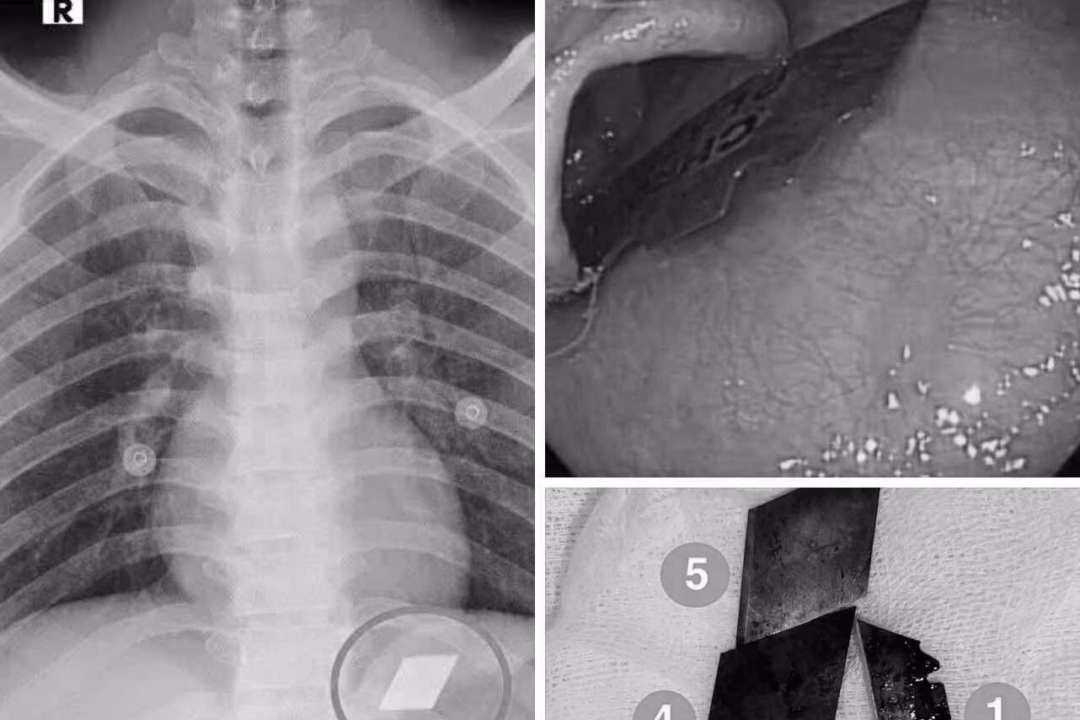

Ngày 10/7, Khoa Hồi sức cấp cứu – Bệnh viện Đa khoa Bình Dương đã tiếp nhận một trường hợp cấp cứu hiếm gặp. Bệnh nhân P.V.L, 26 tuổi, được nhập viện trong tình trạng nuốt nhiều dị vật kim loại sắc nhọn, bao gồm dao rọc giấy và dao lam. Sau khi thăm khám và chụp X-quang, các bác sĩ đã phát hiện các dị vật cản quang tại vị trí dạ dày.

Các bác sĩ đã ngay lập tức chỉ định nội soi cấp cứu để gắp bỏ dị vật. Quá trình thực hiện thủ thuật đòi hỏi sự phối hợp chặt chẽ giữa ê-kíp nội soi và gây mê. Sau nỗ lực của đội ngũ y tế, các bác sĩ đã thành công gắp 4 lưỡi dao rọc giấy ra khỏi dạ dày và một phần lưỡi dao lam mắc tại vùng hạ họng – miệng thực quản.